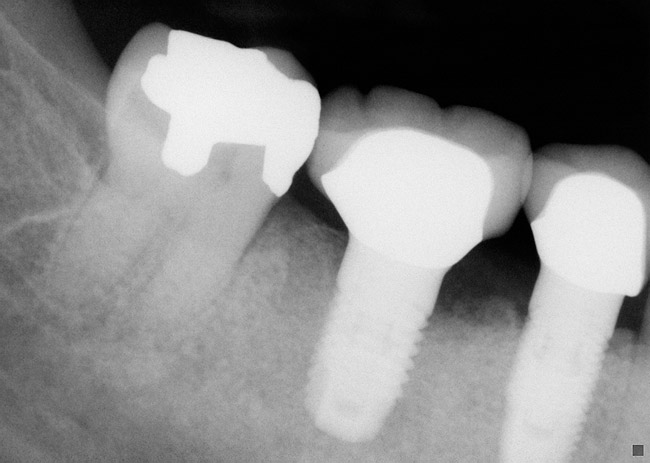

Figure 1  Periapical radiograph of a failed implant with peri-implantitis. Bleeding on probing and pus from the mesial pocket was present.

Figure 1